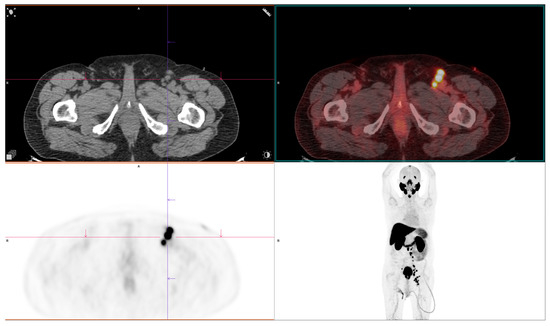

2.4. PSMA-Targeting Radiopharmaceutical PET/CT